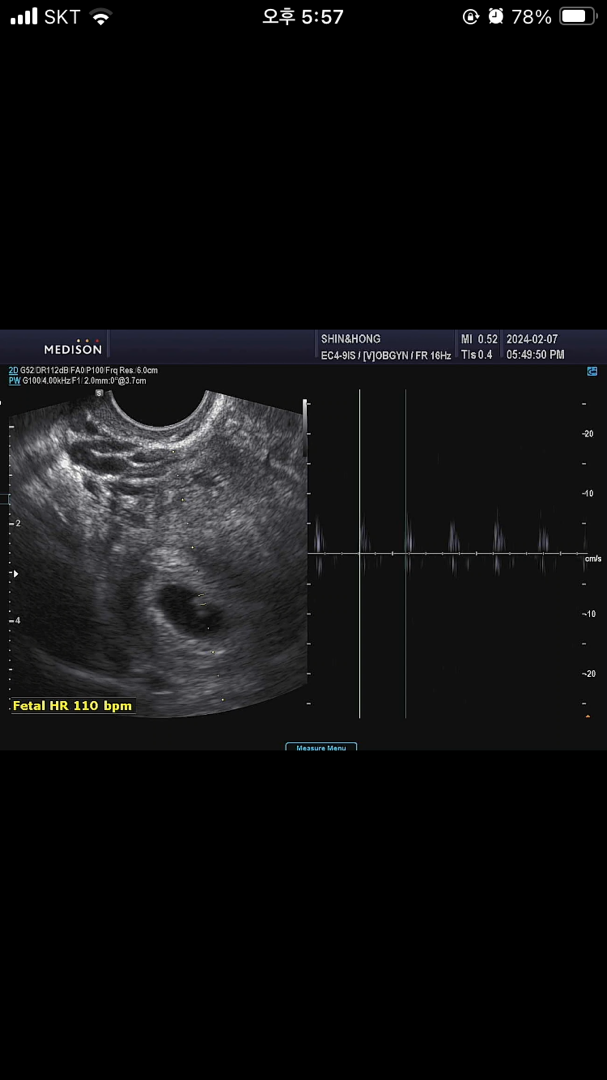

6주1일 아기는 0.37cm 심박수는 110이래요 주수에맞게 잘 크고있는거겠죠??

103~126 6주 심박수래요>< 잘크고 있네요!!